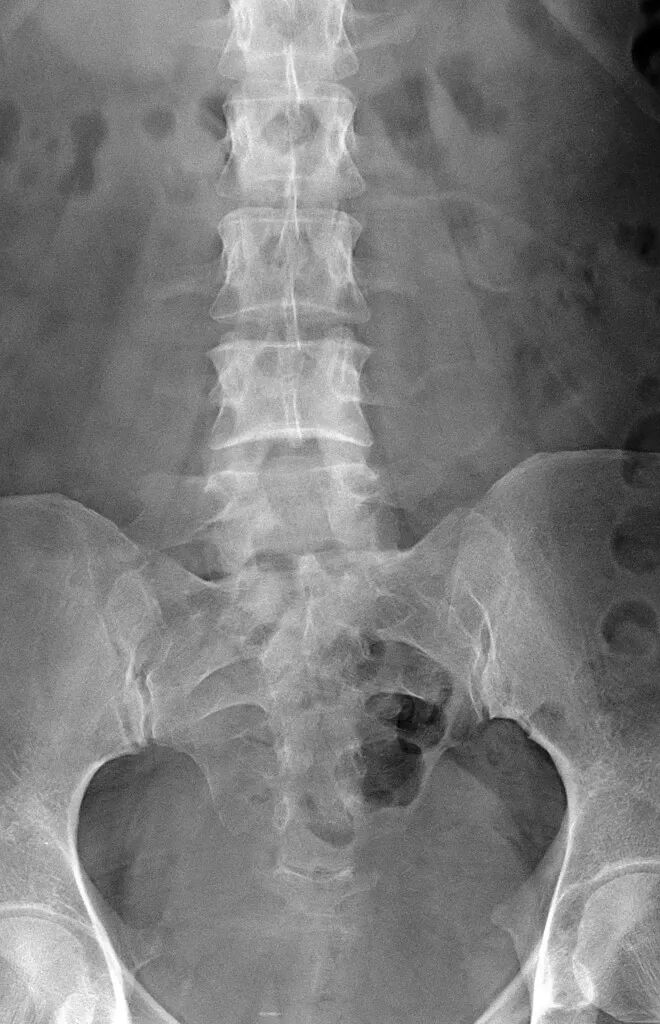

腰椎骶化及骶椎腰化均是椎骨发育的异常,腰椎骶化是指第五腰椎外型类似骶椎形态,并构成骶骨块的一部分,一侧或两侧横突肥大呈翼状,与骶骨发生融合或形成假关节。骶椎腰化是指第一骶椎演变成腰椎样形态,即第一骶骨从筋骨块中游离出来形成第6个腰椎。

这是一个最关键和准确的鉴定方法,国内著名骨放射学家杨世埙教授指导过,只要大家留意关注腰椎横突"三长/四翘/五宽",L3横突是最长的,L4横突是上翘的,L5横突最宽,特别用在胸椎腰化合并L5骶化的时候比较实用。

1984年,Castellvi 提出LSTV分类系统将移行椎分为Ⅰ-Ⅳ型。

Ia型(单侧)和Ib型(双侧):横突肥大宽度超过19mm

IIa型(单侧)和IIb型(双侧):横突与骶骨相接触形成假关节

IIIa型(单侧)和IIIb型(双侧),横突与骶骨发生骨性融合

IV型:一侧横突与骶骨形成假关节,另一侧形成骨性融合

目前,腰骶移行椎以 Castellvi 的分类方法最为常用。其主要根据横突形态及其与骶骨、髂骨是否融合或形成假关节而分为 4 型,Ⅰ、Ⅱ、Ⅲ型又根据单、双侧分为A、B两个亚型。

正常I型:主要为腰5横突发育不良,横突宽度大于19mm,并将其分为两个亚型Ia(单侧横突发育不良)或Ib(双侧横突发育不良)

L5 右侧横突肥大,为 Ⅰa 型

L5 双侧横突肥大,为Ⅰb 型

II型:表现为不完全的腰椎骶化,具有增宽的横突,并且和骶骨形成假关节,并将其分为两个亚型IIa(单侧关节形成)或IIb(双侧关节形成)

L5 左侧横突肥大,假关节形成,为 Ⅱa 型

L5 双侧横突肥大,假关节形成,为 Ⅱb 型

III型:单侧(IIIa)或双侧(IIIb)腰椎完全骶化,腰5横突与骶骨完全骨性融合

L5 右侧横突肥大与骶骨发生骨性融合,为 Ⅲa 型

L5 双侧横突与骶骨骨性融合,为 Ⅲb 型IV型:一侧为II型即腰5横突与骶骨形成假关节,对侧为III型即腰5横突与骶骨形成骨性融合

IV 型即混合型:L5 双侧横突肥大,一侧与骶骨相接触为Ⅱ型表现,另一侧与骶骨形成骨性融合为Ⅲ型移行椎一般不引起症状,但是这种畸形可影响脊柱的稳定并逐渐产生症状,移行椎较正常椎体潜在着更多不稳。由于负重及运动不平衡,而引起腰痛。

它与腰骶部疼痛存在密切的相关性是不可忽视的, 并干扰诊断与之症状相近的其它疾病, 如椎间盘突出、致密性骨炎、强直性脊柱炎等等, 当然这其中有些疾病可以并存, X 线、CT 检查在腰骶部移行椎的诊断中有重要意义, 不仅能对本病做出诊断, 并且有助于鉴别诊断。